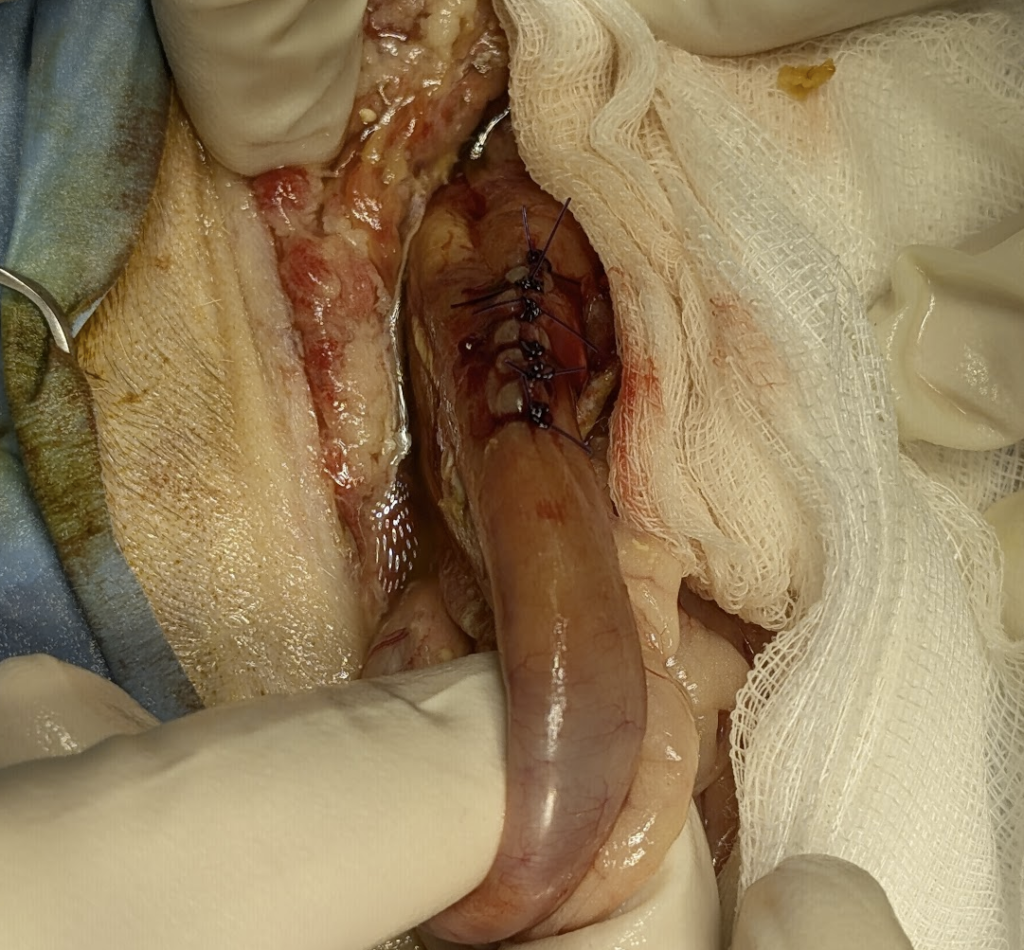

Zabieg wykonywany jest najczęściej metodą laparotomii. Po otwarciu jamy brzusznej identyfikuje się przewód żółciowy wspólny w okolicy więzadła wątrobowo-dwunastniczego. U kota jest to struktura bardzo cienka, podatna na uszkodzenia, dlatego manipulacja musi być minimalna i precyzyjna. Po zlokalizowaniu miejsca zwężenia wykonuje się kontrolowaną kaniulację przewodu, a następnie wprowadza stent o odpowiedniej długości i jak najmniejszej średnicy, która zapewnia trwałą drożność. Stent powinien przechodzić przez obszar zwężenia i kończyć się w dwunastnicy, umożliwiając fizjologiczny odpływ żółci. Na tym etapie kluczowa jest kontrola szczelności i unikanie nadmiernego ucisku na ścianę przewodu.

Dlaczego jest to zabieg trudny i rzadki

Stentowanie dróg żółciowych u kota należy do najbardziej wymagających procedur w chirurgii hepatobiliarnej. Wynika to z mikroskopowej anatomii przewodów żółciowych, ich bliskiego sąsiedztwa z trzustką i dwunastnicą oraz wysokiego ryzyka powikłań w przypadku nawet niewielkiego błędu technicznego. Dodatkowym problemem jest fakt, że większość pacjentów trafia na zabieg w stanie ciężkim, z zaawansowaną żółtaczką, zapaleniem trzustki i zaburzeniami metabolicznymi. Z tych powodów procedura ta wykonywana jest jedynie w wyspecjalizowanych ośrodkach dysponujących odpowiednim doświadczeniem i zapleczem.